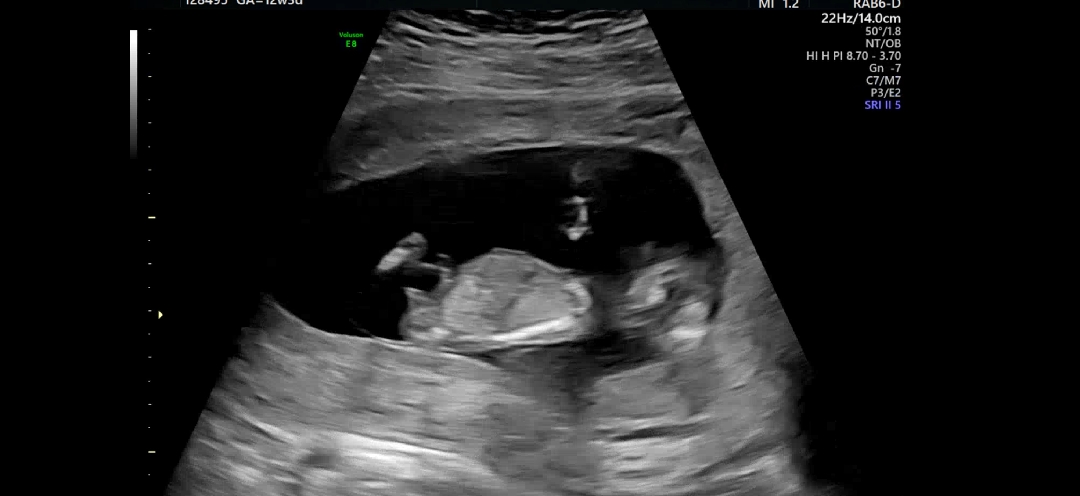

각도법 한번만 봐주세요...ㅎ

아들이냐.. 딸이냐..댓글부탁드립니다!